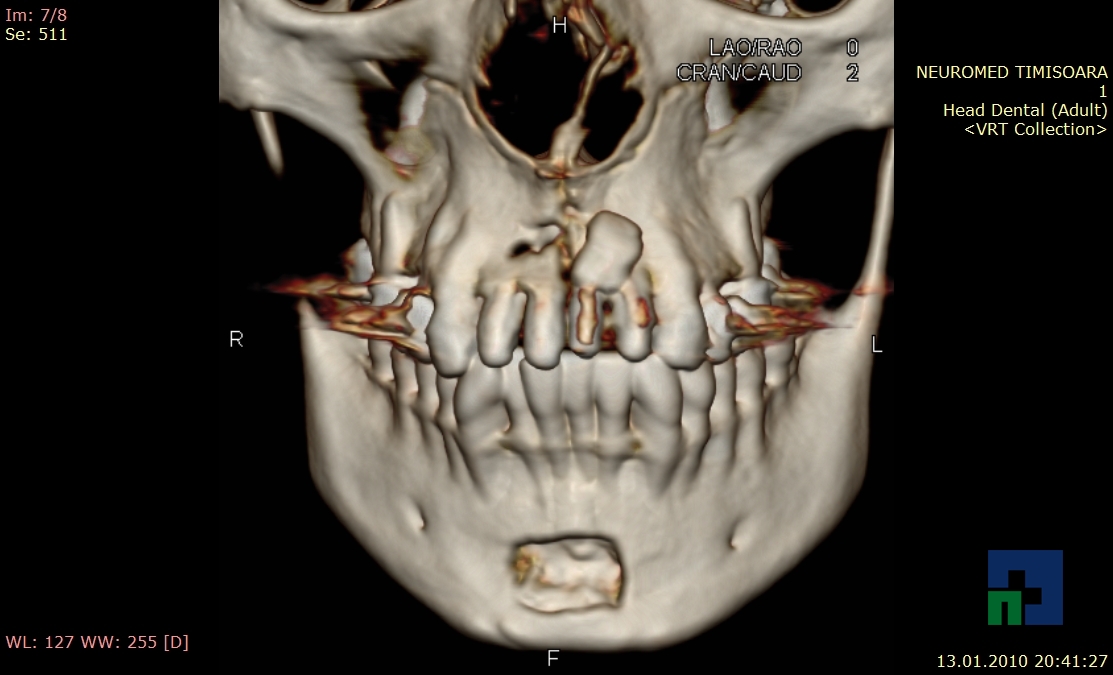

- Diagnosticul fracturilor:

-

- Unice

- Multiple

- Cu înfundare

- Complexe cranio-sinusale

- Complexe cranio-etmoidale

- Complexe cranio-orbitare

- Complexe cranio-faciale